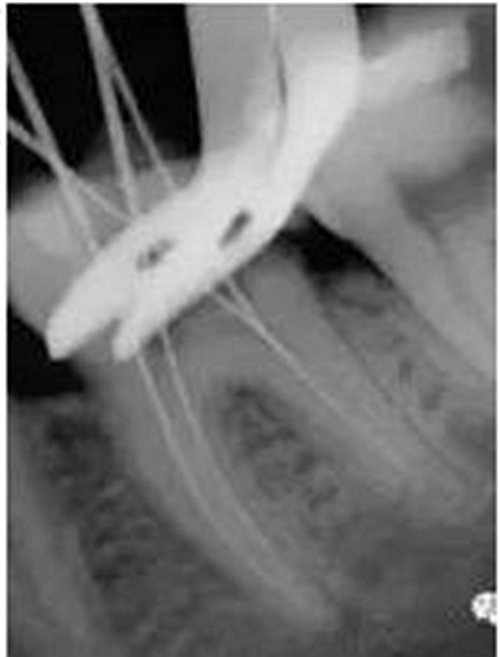

最后來(lái)玩一個(gè)根管治療質(zhì)量的評(píng)估——下圖是武大彭彬教授的一個(gè)病例,仔細(xì)觀察可以挑出一點(diǎn)問(wèn)題,但問(wèn)題事出有因!看看你的“眼力”如何——問(wèn)題在那里?教授的專(zhuān)業(yè)水平是不用懷疑的,那么事出的原因可能是什么?

問(wèn)題答案:這個(gè)病例的問(wèn)題主要反應(yīng)在開(kāi)髓的洞形修整,注意觀察該牙X-RAY的左側(cè)洞壁,如果常規(guī)情況制備成這樣是由于裂鉆破壞了洞壁和洞底所形成的臺(tái)階。如果評(píng)估根管治療的質(zhì)量那是要扣分的!但這個(gè)病例仔細(xì)觀察洞壁形態(tài)就可以看出:該病例屬于再治療的病例,因此還是屬于一個(gè)理想的病例。